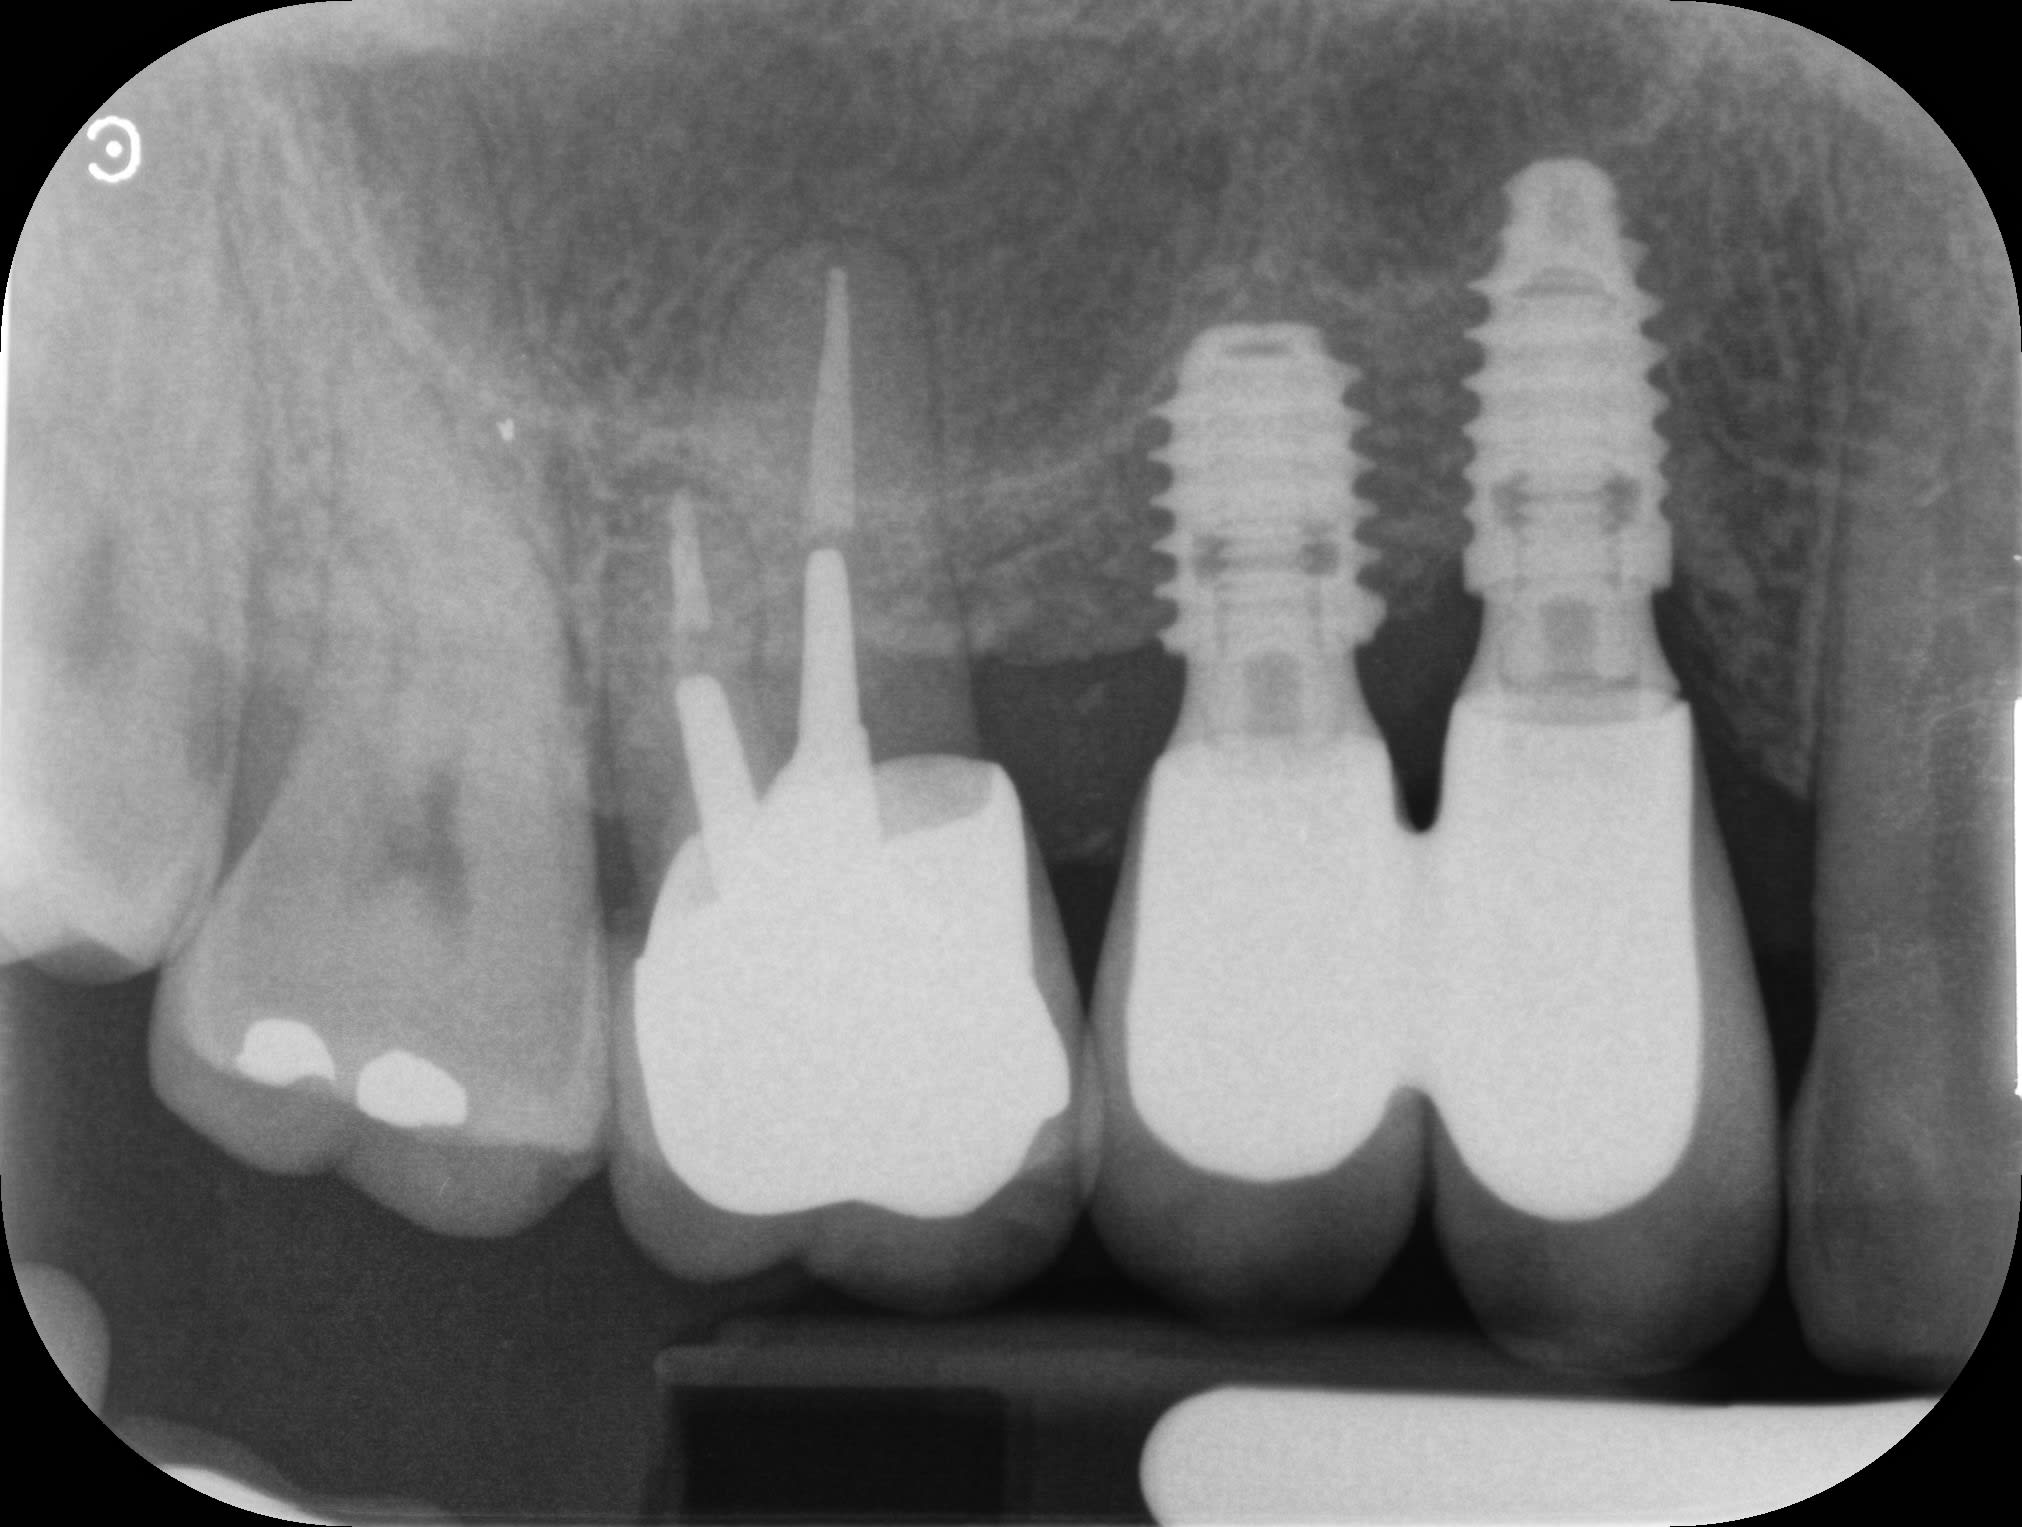

Un petit cas fini il y a deux ans, de l'omni pratique de bout en bout.

Est-ce bien raisonnable? ou trop de facteurs de risque.

Je me pose toujours la question.

Je pense que chez un spécialiste la molaire serait aujourd’hui un implant et pas une molaire avec une amputation radiculaire.

Avec des implants courts au maxillaire, la solidarisation ne me choque pas, au contraire.